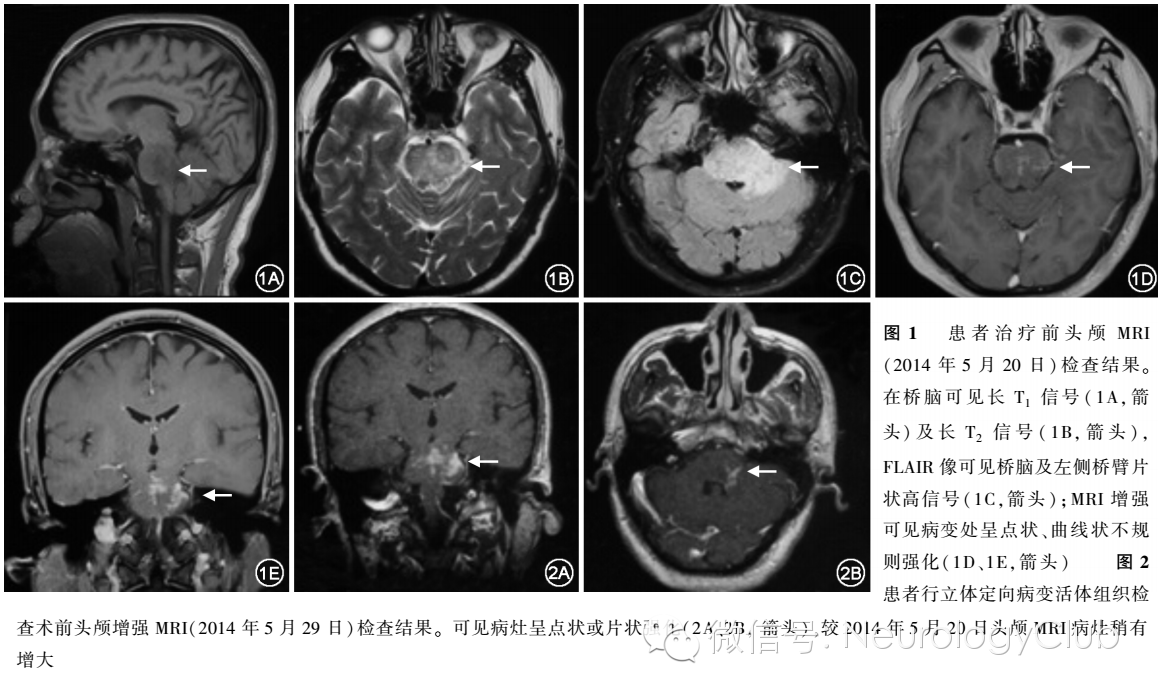

头颅MRI[2014年5月20日(图1),2014年5月29日(图2)]:桥脑及左侧桥臂可见到斑点状、线状长T1、T2异常信号,可见散在点状、线状强化影。 双侧视力均为1.0,双侧视野正常。 脑干听觉诱发电位示右侧V波潜伏期略延长,波间期III-V/I-III>1(正常<1);视觉诱发电位示左、右P100潜伏期均延长,左眼为113ms,右眼为114ms。 双下肢动脉超声检查正常。胸部CT:左肺下叶胸膜下多发陈旧性病变,脾大。

解放军总医院神经内科代表:患者中年男性,亚急性病程,反复发作,以三叉神经、面神经、舌下神经受累症状起病,故考虑定位于相应颅神经及对应脑干核团,辅助检查提示白细胞升高,头颅MRI检查桥脑及左侧桥臂及相邻的小脑可见片状的长T1、长T2信号,增强MRI可见多发点状强化。定性诊断主要考虑原发性中枢神经系统淋巴瘤样肉芽肿(primary central nervous system lymphomatoid granulomatosis)。淋巴瘤样肉芽肿最常累及呼吸系统,亦可有中枢神经系统受累,约占30%,多为颅内多发病灶,可累及皮质、基底节区、脑干、小脑等,头颅MRI于T2相上可见圆形或椭圆形梗死样或占位样高信号病灶,可并有水肿,增强相可见环状、多发点状或线性强化症状可表现为相应病灶部位所对应的精神症状、脑神经损害症状、失语、偏瘫、共济失调等。该患者表现为第5、7、12对脑神经受损症状,影像学检查可于脑桥及左侧桥臂发现长T1、长T2信号,呈斑片状或线样强化,符合该病表现。鉴别诊断:(1)原发性中枢神经系统淋巴瘤好发于免疫缺陷或长期服用免疫抑制剂的患者,多发于额叶、胼胝体及深部白质等近中线部位,文献报道约有43%的淋巴瘤样肉芽肿最终演变成为淋巴瘤,两种疾病较难鉴别。本例患者支持点为临床症状与之较为相符,不支持点为患者脑桥的斑点样及线样强化病灶与淋巴瘤的均匀强化、边界清晰的特点不相符。(2)中枢神经系统脱髓鞘疾病:支持点为患者的第7、12对脑神经受损,视诱发电位提示双侧P100潜伏期延长。 不支持点为患者目前脑桥等病灶部位在脱髓鞘疾病中不常见,且病灶呈片状分布,似有血管炎性病变可能。

北京市复兴医院神经内科代表:患者以颅神经受累症状起病,伴有全身非特异性症状,定性诊断考虑为CLIPPERS该病主要病理表现是桥脑及邻近的组织,包括桥脑臂、中脑、延髓及上段脊髓为主的血管周围为主的T淋巴细胞为主的炎性浸润,对类固醇激素治疗敏感,临床症状主要为桥脑症状,包括桥脑核团发出的纤维的受损,主要表现为共济失调和复视,此外可有构音障碍,但是原始文献中提到构音障碍多数是共济失调型,同时可以有面部、头皮的针刺样感觉异常,其他症状包括非特异性的头部昏沉感、恶心、强哭强笑、耳鸣、震颤、眼震、截瘫、感觉障碍或肢体痉挛的症状。 文献报道本病亚急性病程,自然病程为7-35d,头颅MRI提示桥脑、中脑或小脑斑片状的异常信号,增强可见特征性的“胡椒粉”样高信号,最大的病灶为9mm,绝大部分病灶在1-3mm。 该病治疗主要是静脉给予大剂量的激素冲击。此例患者为亚急性病程,主要临床表现为脑神经受累及全身非特异性的症状,和文献报道相似,头颅MRI有经典的影像学改变。患者首次起病后予抗炎治疗后缓解,考虑是否予以激素治疗?但此后未规律维持使用小剂量激素导致复发。综上,考虑诊断CLIPPERS综合征。

CLIPPERS患者辅助检查中血常规、血生化、自身免疫抗体、AQP4抗体等常规检查多表现为正常。部分患者脑脊液可出现以淋巴细胞为主的白细胞增多,蛋白轻度增高,寡克隆区带在约半数患者中可出现阳性表现。该病较少累及视神经、听神经,其脑干诱发电位多正常。该病影像学特点最为突出。头颅增强MRI在脑桥及周围组织可见“撒胡椒粉”样点状或曲线状散在强化病灶,且多为对称性分布,但Pittock等报道1例患者早期呈偏心性强化病灶,后随病情进展逐渐演变为脑桥及双侧桥臂对称分布。其病灶亦可累及脑桥周围的中枢神经系统,以中脑、小脑中脚为主,于延髓、丘脑、基底节、胼胝体、脊髓等部位较为少见,病灶与脑桥距离越远, 病灶数量通常越少,并不表现为明显占位效应。但本例患者左侧桥脑可见轻度水肿,存在一定的占位效应,与周雁等报道的CLIPPERS患者小脑肿胀明显,具有占位效应相符。此类表现应注意与瘤样脱髓鞘病相鉴别。

综上,目前CLIPPERS尚无明确诊断标准,临床诊断主要依靠临床表现、影像学改变、病理学特点及对类固醇激素治疗敏感等特点,甚至有报道认为其并不是一个独立的疾病实体,可能为颅内B淋巴细胞源性淋巴瘤的早期病变,故关于该疾病的本身仍需深入研究。本例患者主要症状为颅神经受损症状,头颅MRI可见经典“撒胡椒粉”样强化,且对类固醇激素治疗敏感,故患者临床诊断符合CLIPPERS。 但本例患者也存在一些不典型之处:(1)本例患者首次发病为2014年3月,此后予对症治疗后症状自行缓解,于2014年5月18日再次出现上述症状。该患者起病缓慢,表现出的类似缓解复发病程,此在国内外文献中均罕有报道。(2)本例患者早期头颅MRI在双侧脑桥及桥臂均可见大量散在病灶,以左侧为著,与Pittock等、Simon等所报道的对称性病灶存在一定的差异,但Pittock等亦报道了1例偏心性病灶逐渐转变成为对称性病灶的病例,故此患者仍需进一步随访。(3)文献报道中CLIPPERS患者治疗上均为大剂量激素冲击治疗,而本例患者仅应用甲泼尼龙40mg/d小剂量激素维持治疗,症状出现明显改善,与文献报道存在差异,此亦说明该病对类固醇激素敏感的特点。此例患者在治疗中使用大剂量激素冲击治疗是否可以获得更佳的疗效尚需进一步研究。(4)根据文献报道,CLIPPERS患者多无神经电生理改变,但本例患者视诱发电位均表现出异常,病理检查提示炎性脱髓鞘病变,需与多发性硬化(multiple sclerosis,MS)、视神经脊髓炎谱系疾病(neuromyelitis optica spectrum disorders,NMOSD)等相鉴别。 本例患者脑干部位出现大量散在病损,但临床症状较轻,此“病灶多症状轻”的表现及对激素治疗极其敏感的特点与MS的临床症候不符;其次此患者影像学改变不符合MS的时间、空间上多发颅内病灶的相关诊断标准。故尽管由于患者拒绝及外科首诊不重视腰椎穿刺等原因,缺乏脑脊液相关检查,仍不支持MS的诊断。患者虽未完善AQP4检查,但其核心临床症状、影像学改变等均与NMOSD诊断标准相去甚远,目前亦暂不考虑NMOSD的可能性。(5)文献报道CLIPPERS患者首发表现多为步态共济失调、视物模糊等症状,面部麻木为首发症状的报道较少。